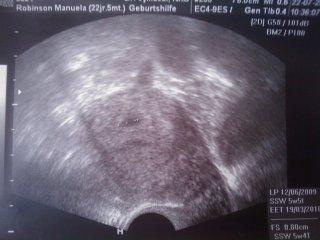

ich komme gerade vom FA und man konnte endlich etwas sehen!!!!! letzten donnerstag war ich in der 5. SSW und er konnte nix sehen und das hat mir schon sorgen gemacht aber heute endlich die erleichterung ich hab eine kleine fruchhoele 8 mm gross!! ich muss am donnerstag nochmal hin um zu gucken ob das herzchen schlaegt aber da bin ich mir auch ganz sicher!! ich freu mich soooo sehr und bin so erleichtert! hier mal ein bild hoffe ihr koennt es erkennen

Bild zu HURRRRAAAAAA - Forum für März - Mamis